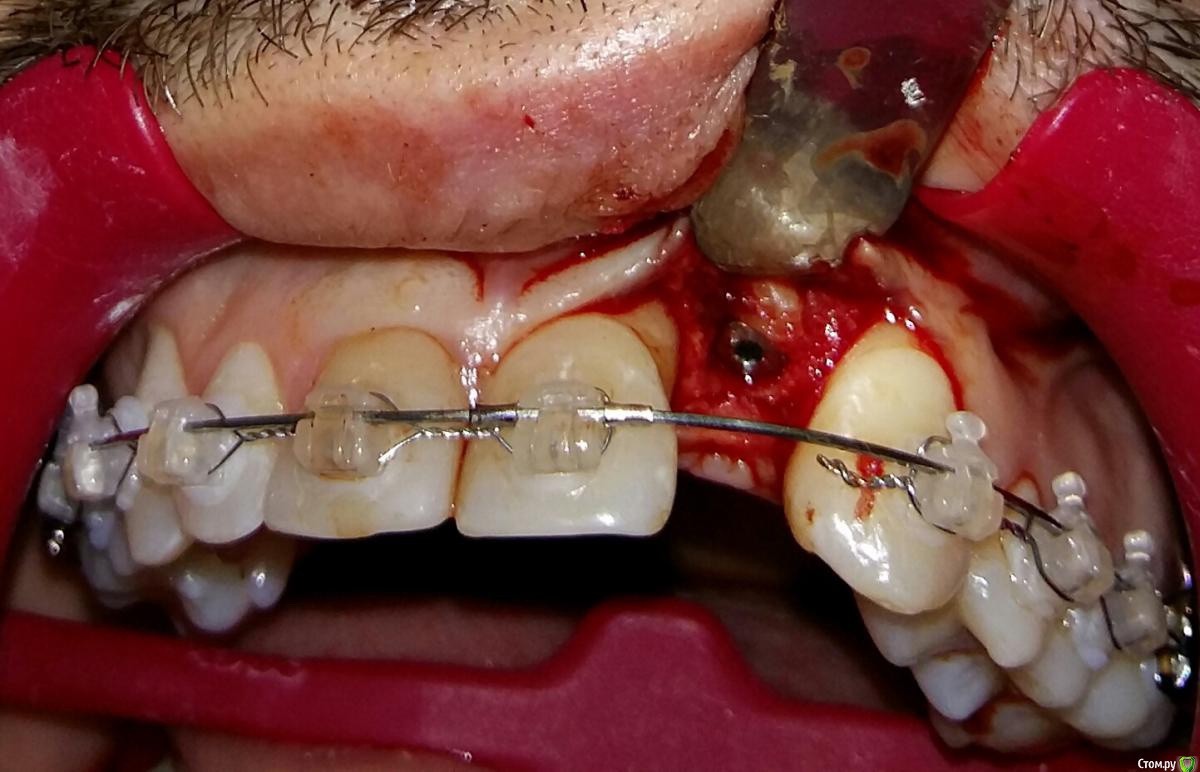

Kostoprav Опубликовано 8 июля, 2015 Поделиться Опубликовано 8 июля, 2015 ИЗНАЧАЛЬНАЯ СИТУАЦИЯ ПОЛУЧИЛОСЬ сори что нет фото до имплантации. Блок взял с тела челюсти, фиксировал двумя винтами (во время имплантации выкрутил только один), присыпал gen os, укрыл дермой-получил заметный прирост слизистой) имплант альфадент 3,75х11,5 2 Ссылка на комментарий

Kostoprav Опубликовано 8 июля, 2015 Автор Поделиться Опубликовано 8 июля, 2015 Видно что блок прирос. ЗдоровоОстальное оценить сложноМне нравится положение импланта в плане оси.Но уровень заглубления не ясенТакже не видно прироста десныВ общем мало данных для оценкиНо опять же вам именно она и нужна?по вестибюлярной поверхности заглубил приблизительно на 1мм с небной больше получилось. слизистая по сравнению с первым разом значительно толще стала, доказать к сожалению не могу так как не делал фото(: я выложил этот пост не только ради оценки, может кому из начинающих данный случай сгодиться 3 Ссылка на комментарий